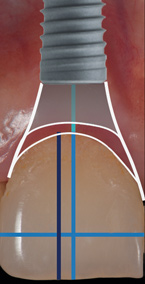

(3.) Implant placement at site No. 8 that is mesiodistally centered with the gingival zenith, exhibiting a gingival contour that is harmonious with the abutment contour.

Figure 3

Given the importance of these hard- and soft-tissue relationships, in order to achieve an optimal esthetic and functional outcome in the anterior maxilla, it is proposed that, mesiodistally, implants should be centered in line with the gingival zenith rather than centered within the available restorative space (Figure 1 through Figure 3).

The digital wax up allowed the implant position to be planned based on the ideal prosthetic position of the final restoration (Figure 14). The planned implant position adhered to the aforementioned guidelines for ideal implant placement regarding the buccal, interproximal, and apical bone, and its platform would be located 4-mm apical to the planned restorative margin. In the coronal plane, the implant was centered with the gingival zenith in a position that was located approximately 1-mm distal to the midline of the edentulous space. Following implant planning, a tooth-supported surgical guide was designed and then 3D-printed to facilitate fully guided surgical implant placement.